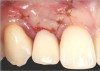

Case 3: Congenitally missing lateral incisors at the sites of teeth Nos. 7 and 10. Both sites were treated simultaneously. (Treatment at the site of tooth No. 10 is illustrated.)

Figure 19

Fig 20. Papillae-sparing incisions were developed both horizontally and vertically. The pedicle flap was elevated, exposing a thin ridge.

Figure 20

Fig 21. A dental implant was placed at the site of tooth No. 10. A defective buccal ridge was noted.

Figure 21